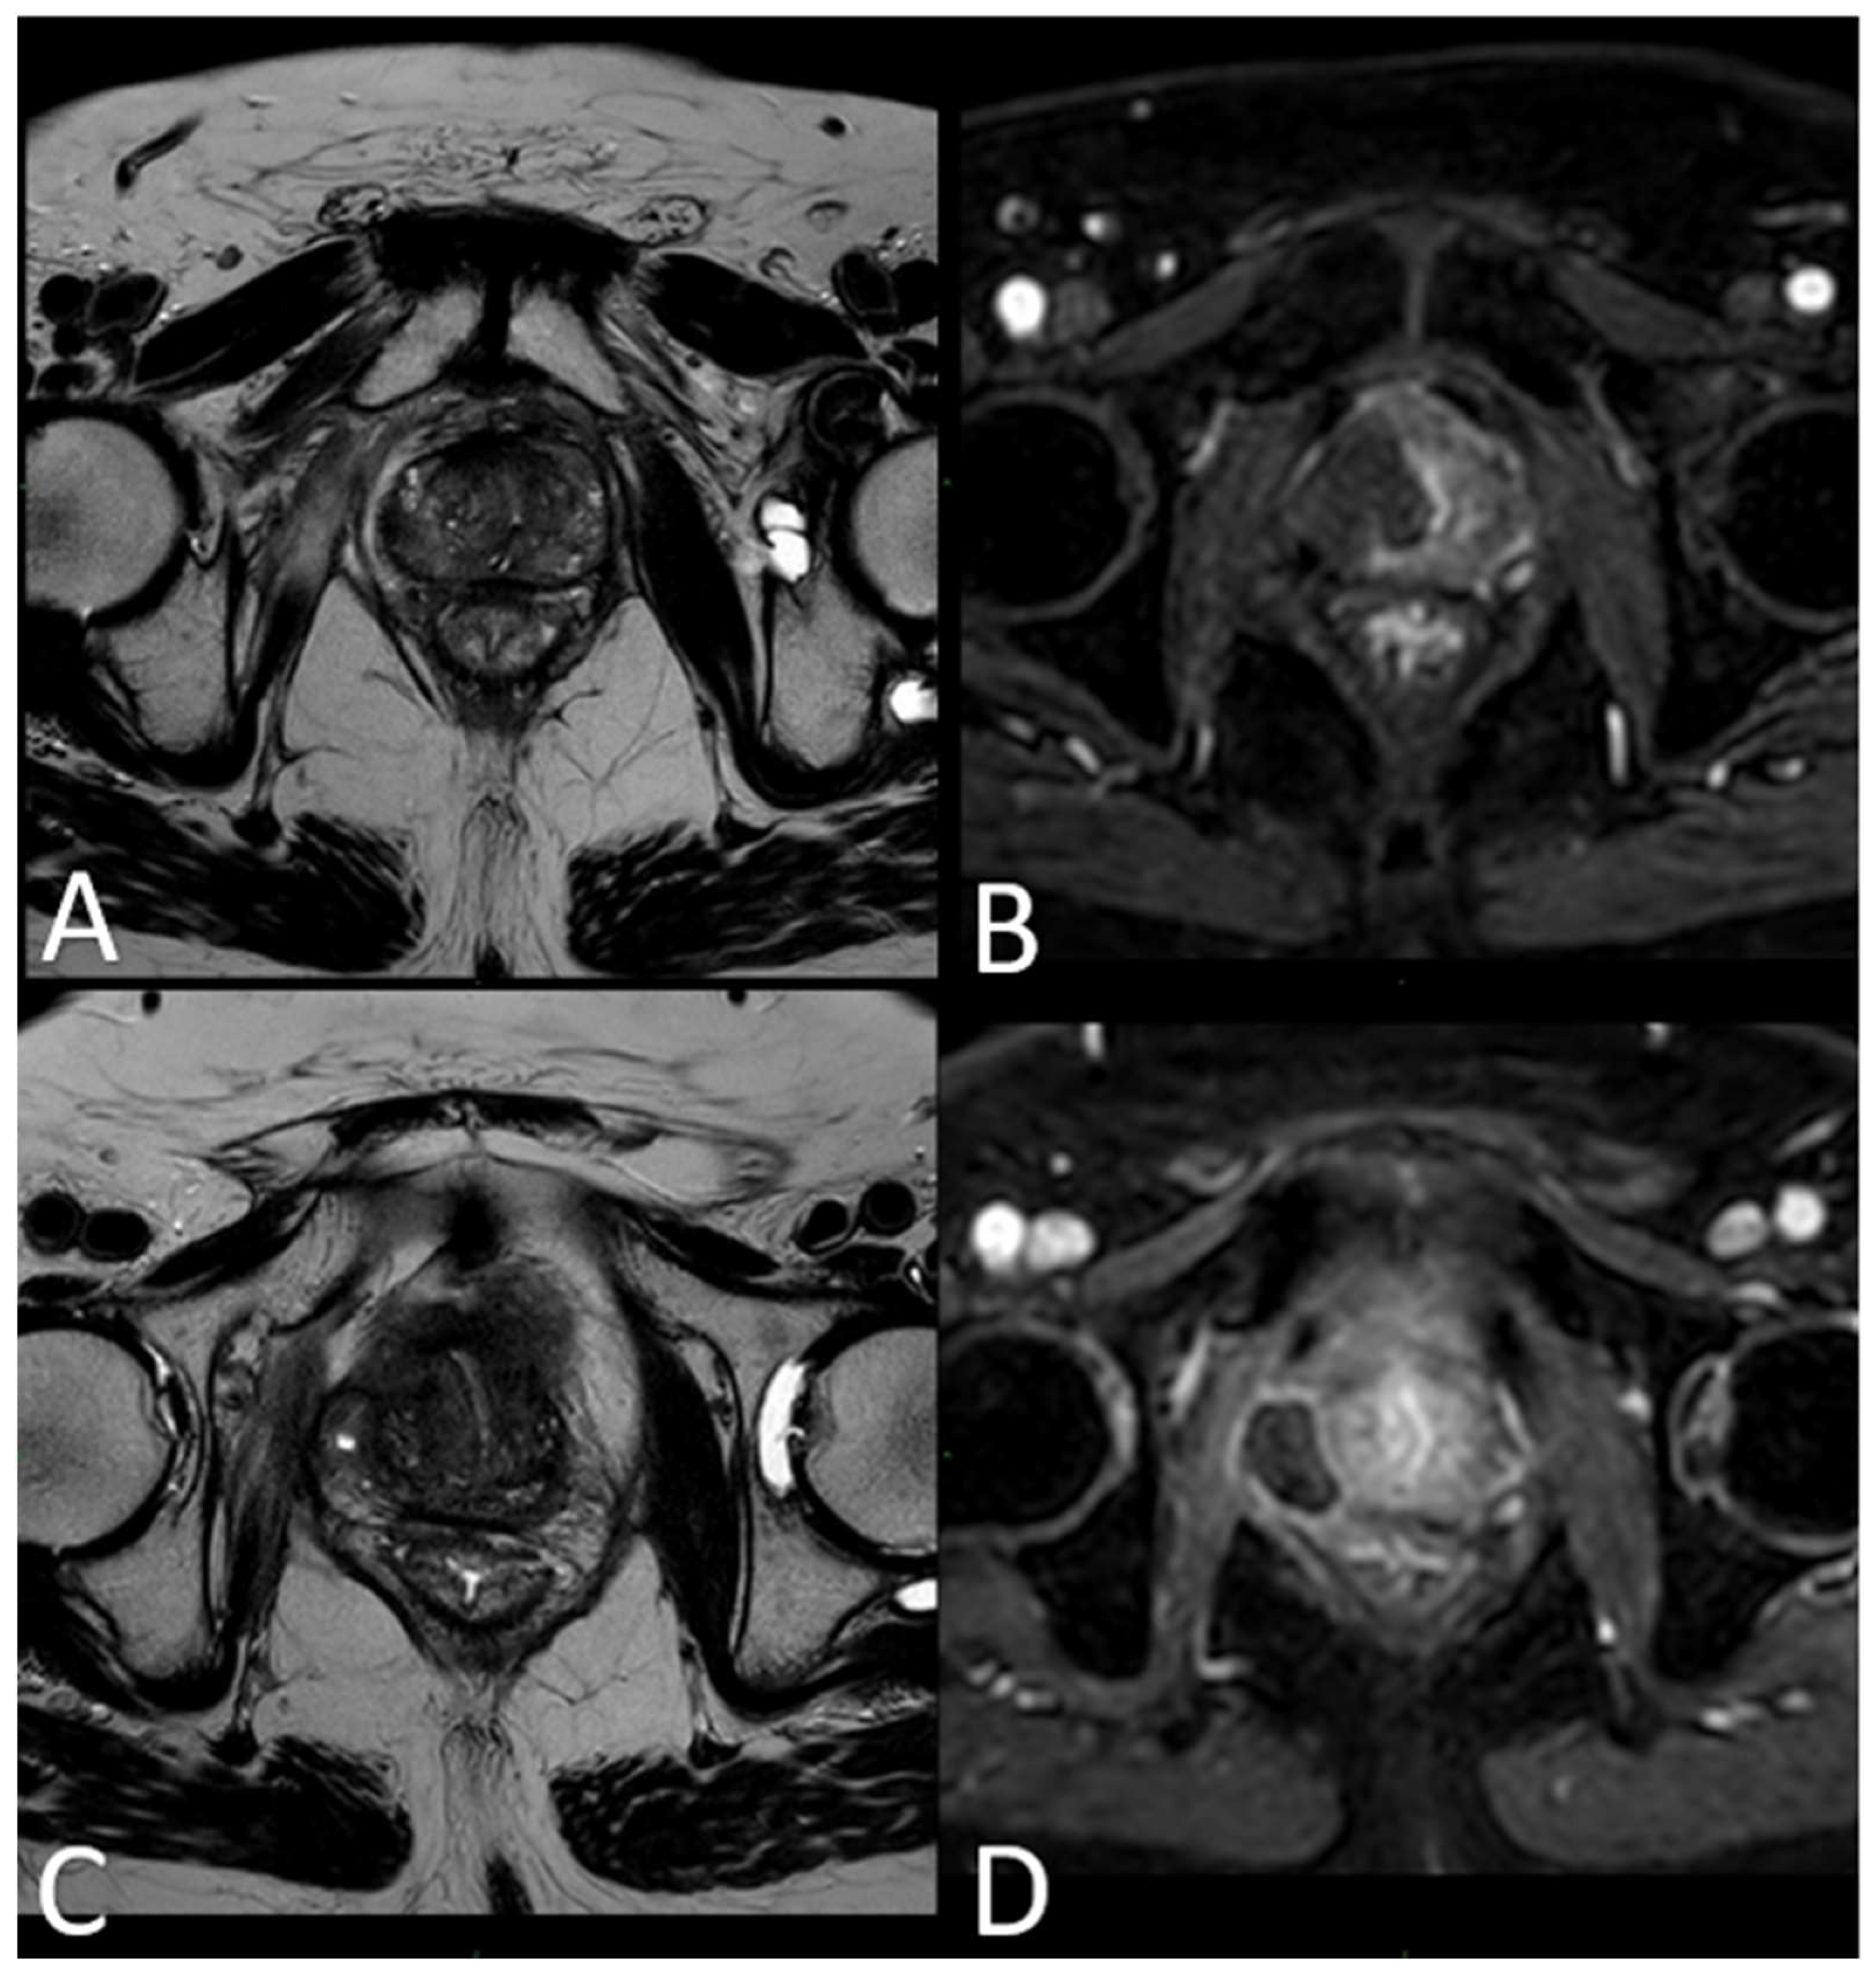

3.2. mpMRI-Derived Results